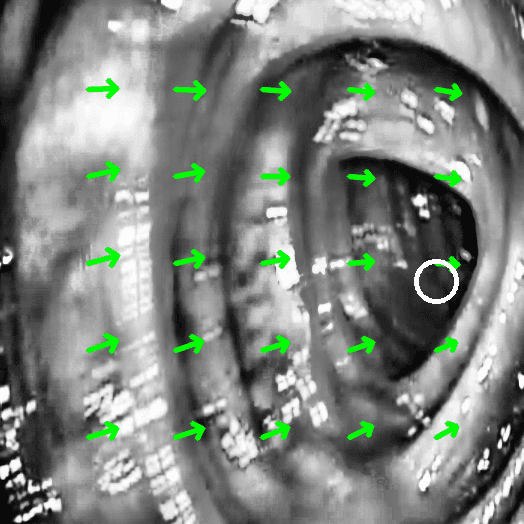

The software used classical computer vision techniques to asses multiple ways of measuring the quality of the examination. Clarity of the image, how well the patient has been prepared and so on. The most challenging part was a map that was going to approximate directly doctor’s technique in operating the endoscope.

For that optical flow was used to calculate the distance traveled by the endoscope in patient’s body and a map was outputted real time that approximated the examined parts of the colon.